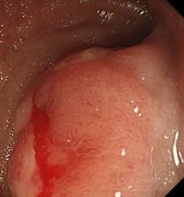

Inflammatory fibroid polyp of the duodenum – Complete endoscopic removal of the IFP (Courtesy Dr. V. Penopoulos)

Abdominal CT scan. Red outline – Inflammatory fibroid polyp of the duodenum (Courtesy Dr. V. Penopoulos)